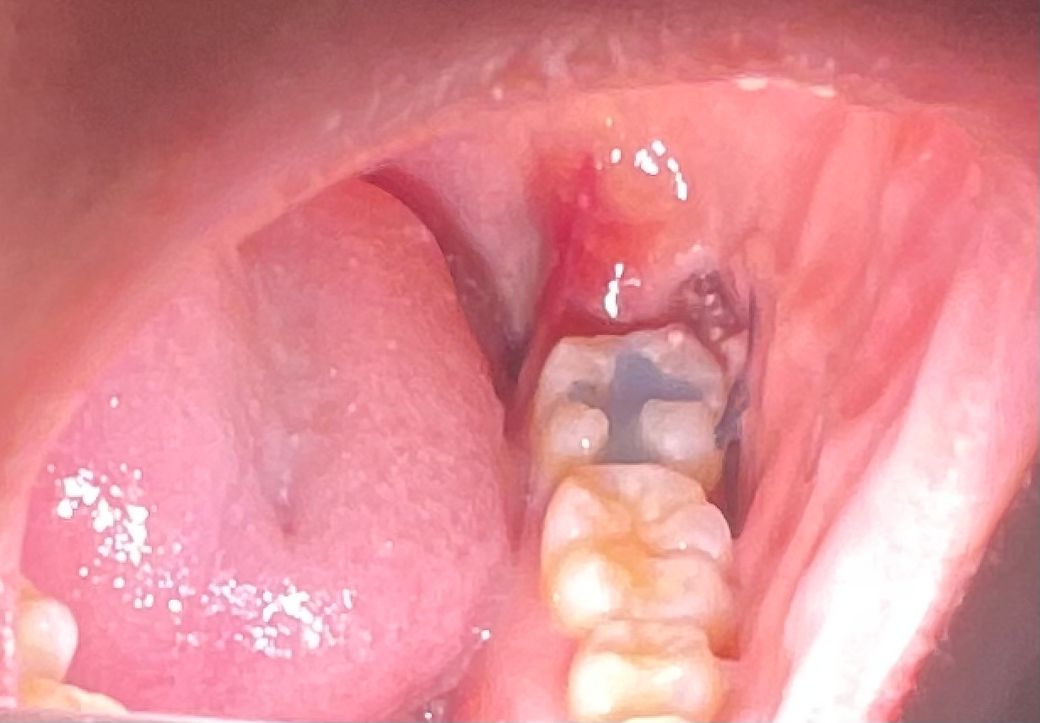

매복사랑니 발치 후 혈전안에 하얀색이 뭔가요?

매복사랑니를 이번주 목요일날 발치하여서 현재 3-4일차 입니다. 사랑니 발치한 자리 혈전에서 하얀색 덩어리들이 보이는데 이게 뭔지 궁금합니다. 처음에는 이물질인줄 알고 물가글을 해보았는데 안없어지는걸로 보니 이물질은 아닌것같은데.. 뭘까요?

그리고 발치한 부분 옆에도 빨갛게 부어올랐습니다ㅠㅠ

• 2번 째 사진

발치한 부위에는 상처가 생기기 때문에 붉은색으로 보일수 있습니다. 발치한 부위에는 이물질등이 들어갈수 있으며 가피가 형성되면 하얀색으로 보일수도 있습니다.

사랑니 발치를 하고나서 잇몸이 치유되는 과정중에 생기는 자연스러운 현상입니다. 걱정하지않으셔도 됩니다.

발치 후 생기는 다양한 염증 육아조직으로 보입니다 걱정 안하셔도 됩니다 발치 후 주의사항 잘 지켜주세요